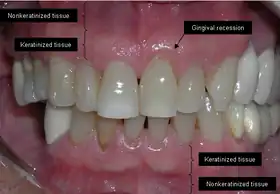

Anatomy

Gums showing recession

The soft tissue in the oral cavity is classified as either keratinized or nonkeratinized based on the presence of keratin in the epithelium.[4] In health, the soft tissue immediately around the teeth is keratinized and is referred to as keratinized tissue or gingiva. Alveolar mucosa is non keratinized oral epithelium and is located apical to the keratinized tissue, delineated by the mucogingival junction (MGJ). It should also be pointed out that mucosa can surround a tooth in health.[5] Nonkeratinized tissue also lines the cheeks (buccal mucosa), underside of the tongue and floor of the mouth. The lips contain both non-keratinized tissue (on the inside) and keratinized tissue on the outside, demarcated by the vermillion border. The dorsum of the tongue is keratinized and features many papillae, some of which contain taste buds.[6]

Exposure of the tooth root due to loss of keratinized tissue around the neck of a tooth is referred to as gingival recession. This can result in sensitivity or pain from the exposed tooth root surface (dentin is more permeable and soft compared to enamel and dentin is what makes up the tooth root).[7] Recession may also cause an unasthetic appearance especially if located in the anterior dentition (front teeth). While not all cases of gingival recession require surgical correction, there are various options if that is what the patient desires.[8] It should be reinforced that recession left untreated will not result in tooth loss, contrary to popular belief. Also, recession that is left untreated can be maintained and the inflammation kept at bay with proper brushing and oral hygiene technique.[5] On the other hand, if one desires to pursue corrective therapy, there are a wide variety of techniques ranging from autograft (your own tissue, usually taken from the palate), allograft (someone else's tissue, cadaver), xenograft (animal, usually porcine or bovine) or simply repositioning of the tissue native to the site.[9] The benefits of corrective therapy often result in decreased sensitivity through coverage of the root surface in addition to a gain in the keratinized tissue mentioned beforehand.